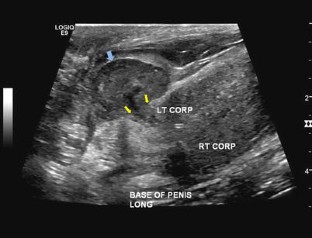

The “eggplant penis” sign

Fig. 2

• Corpus Cavernosa